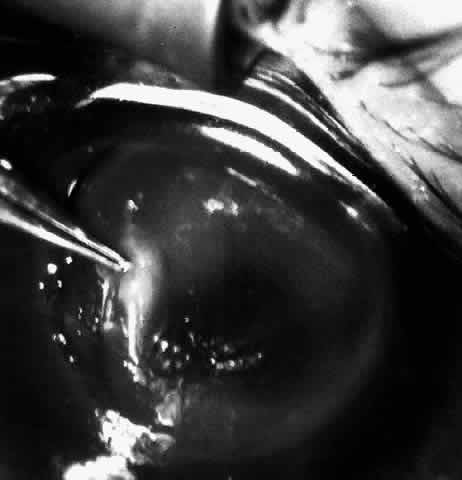

Next, an angled lamellar dissector such as one would use to dissect a trabeculectomy flap is used to create a 1-mm lamellar pocket in the peripheral direction for 360° around the cornea at the base of the trephined incision. In the past a small strip of cornea was excised centrally from the inner aspect of the trephine incision. This keratectomy has been found unnecessary and the procedure may be more easily reversed without the keratectomy. Then the tissue lens is draped over the cornea stroma-side-down and centered on the annular incision (Fig. 9).

Fig. 9. Hydrated lens is placed on the front of the cornea.